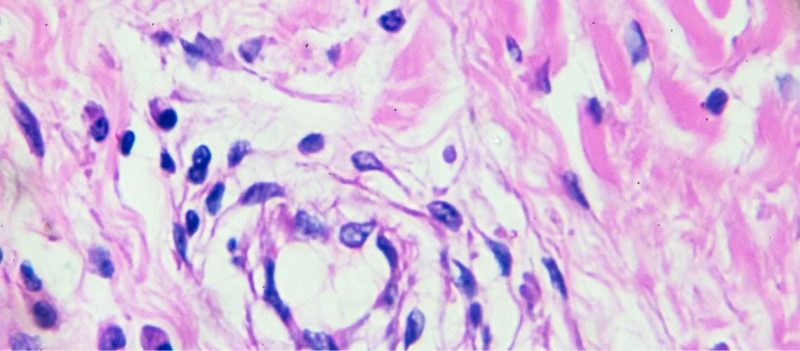

Diffüz Büyük B-Hücreli Lenfoma

Diffüz Büyük B Hücreli Lenfoma (DLBCL) en sık görülen non-Hodgkin lenfoma alt türlerinden biridir ve [...]